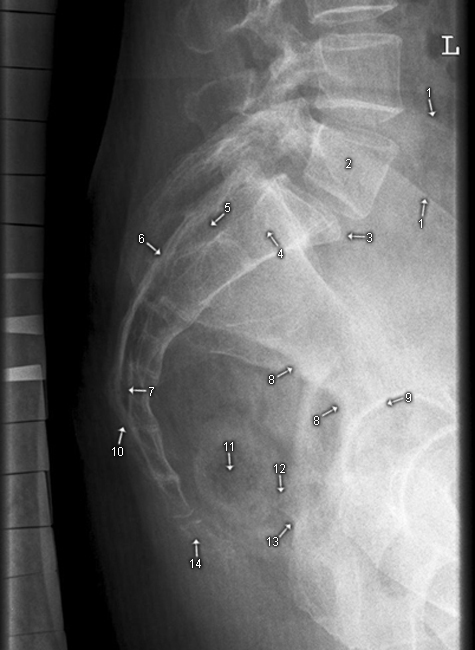

LWS seitlich

1. Foramen intervertebrale

2. Wirbelkörpergrundplatte

3. Wirbelkörperdeckplatte

4. Intervertebralraum

5. Processus transversus

6. Processus articularis inferior

7. Processus articularis superior

8. Processus spinosus

9. Crista iliaca

10. Promontorium

11. Os sacrum